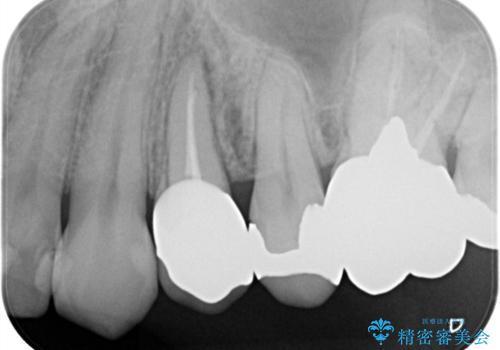

根管治療した場合は速やかに被せ物による修復が必要です。

大きい虫歯 根管治療〜オールセラミッククラウン